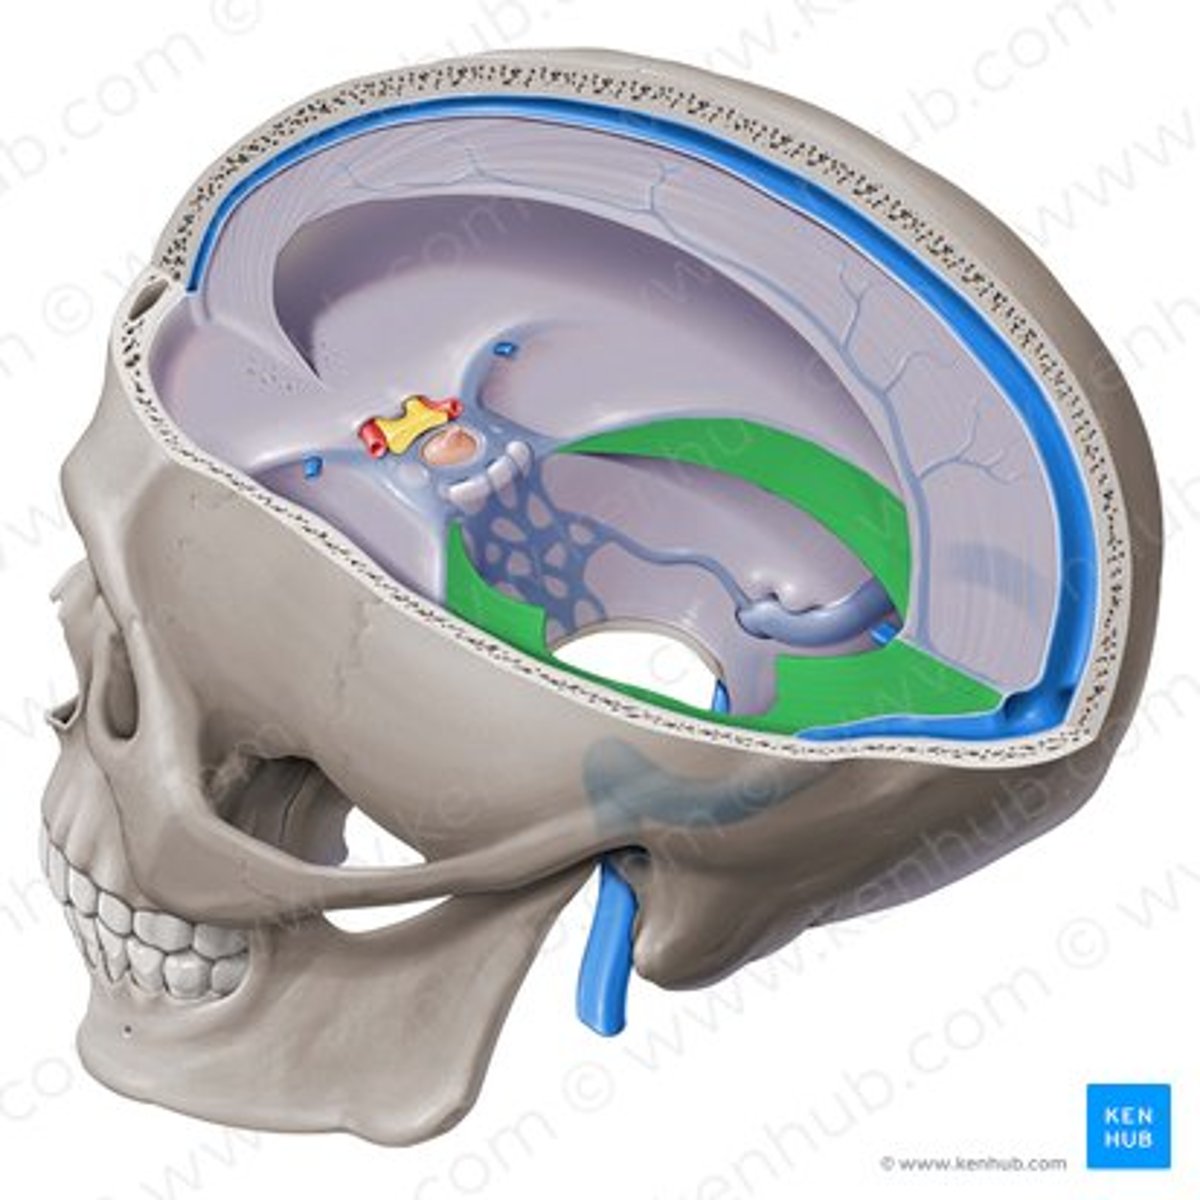

falx cerebri

sickle shaped, separates two hemispheres

tentorium cerebelli

shelf-like, separates cerebellum from cerebrum

tentorium cerebelli

falx cerebri